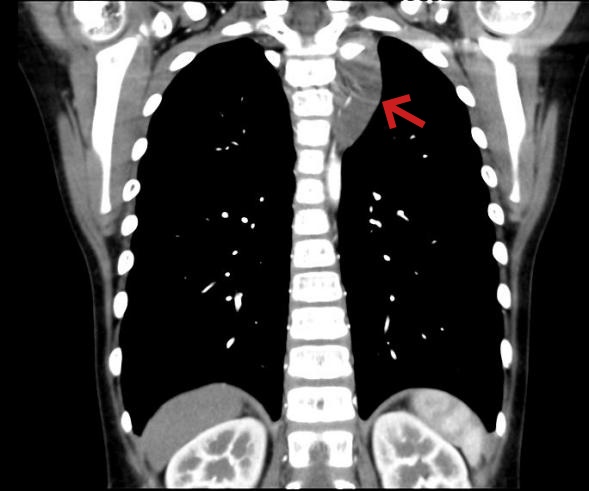

箭头所示为长入椎间孔之纵隔肿瘤

大约2个月前,男童一一(化名)经常哭喊着自己的左侧胸部会出现针刺样的疼痛,休息片刻后疼痛症状会有所缓解。1周前,一一因流行性感冒到儿童医院呼吸科门诊,胸部CT检查时发现,其左侧纵膈内有一个和鸡蛋差不多大小的肿瘤。进一步检查后发现,这是一个生长在左侧后上纵膈胸椎旁的神经来源肿瘤,而且肿瘤已经往椎间孔里生长,虽然还没有侵犯到脊髓,但想要通过手术完整切除不仅难度大、容易损伤脊髓神经,如果切除不干净,肿瘤的残留部分还会导致术后复发。